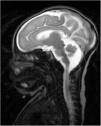

Recién nacido a término con retraso del crecimiento intrauterino a partir de la semana 34. Sin antecedentes gestacionales de interés. No consanguinidad paterna. Parto eutócico. Peso al nacer: 2.470g (p 2, DE: −2,18), talla: 46cm (p 2, DE: −2,3) y perímetro craneal: 30cm (<p 1, DE: −3,21). A las 2h de vida comienza con movimientos de chupeteo que posteriormente se asocian con movimientos clónicos de cara y miembro superior izquierdo de 4min de duración. Presenta episodios similares durante las primeras 24h de vida que ceden con tratamiento con fenobarbital. Se realiza estudio de convulsión neonatal en el que destaca una trombocitosis y un ligero aumento de hormonas tiroideas en analítica sanguínea. Se realiza un electroencefalograma que es normal. En ecografía transfontanelar, se observa un adelgazamiento de cuerpo calloso con una megacisterna magna. Se realiza resonancia magnética cerebral (fig. 1) que describe, además de los hallazgos observados previamente, atrofia parcial de vermis y moderada disminución de la surcación a nivel frontal y occipital compatible con LCH. Requiere tratamiento con fenobarbital, levetiracetam y clobazam por mal control clínico de epilepsia. Al mes y medio de vida se observa colestasis en analítica de control (bilirrubina total de 6,8mg/dl, directa de 5,3mg/dl y gamma-glutamil transferasa de 2.120UI/l). Se amplía estudio de colestasis con estudio alfa-1-atripsina, infeccioso, hormonal, metabólico y ecografía abdominal que son normales. Ante la sospecha de ABEH se decide realizar tratamiento conservador por mal pronóstico de la paciente. Se realiza estudio genético de lisencefalia y defectos de la glicosilación que resultan negativos. A los 7 meses, consulta por fiebre y descompensación de su hepatopatía, pero a pesar del tratamiento médico, fallece por parada cardiorrespiratoria. En autopsia, se confirma la ABEH gracias a la biopsia hepática. Es el primer caso descrito en la literatura de LHC con ABEH. No existen estudios ni se han descubierto mutaciones genéticas que relacionen la LCH con ABEH.